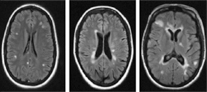

Multiple Sclerosis (current projects)

Quality of Life and Cognition in Multiple Sclerosis (recent project)

We recently worked on a nationwide survey on perceived quality of life and cognition in patients with MS. This study is part of a longitudinal research project and was conducted in 16 European countries. The DBN investigated the relationship between perceived quality of life, clinical disease course, disease severity and social support in patients with MS. The outcomes underline the importance of disease characteristics as well as of social support and promote a multi-facetted treatment approach to ensure good quality of life in MS patients.